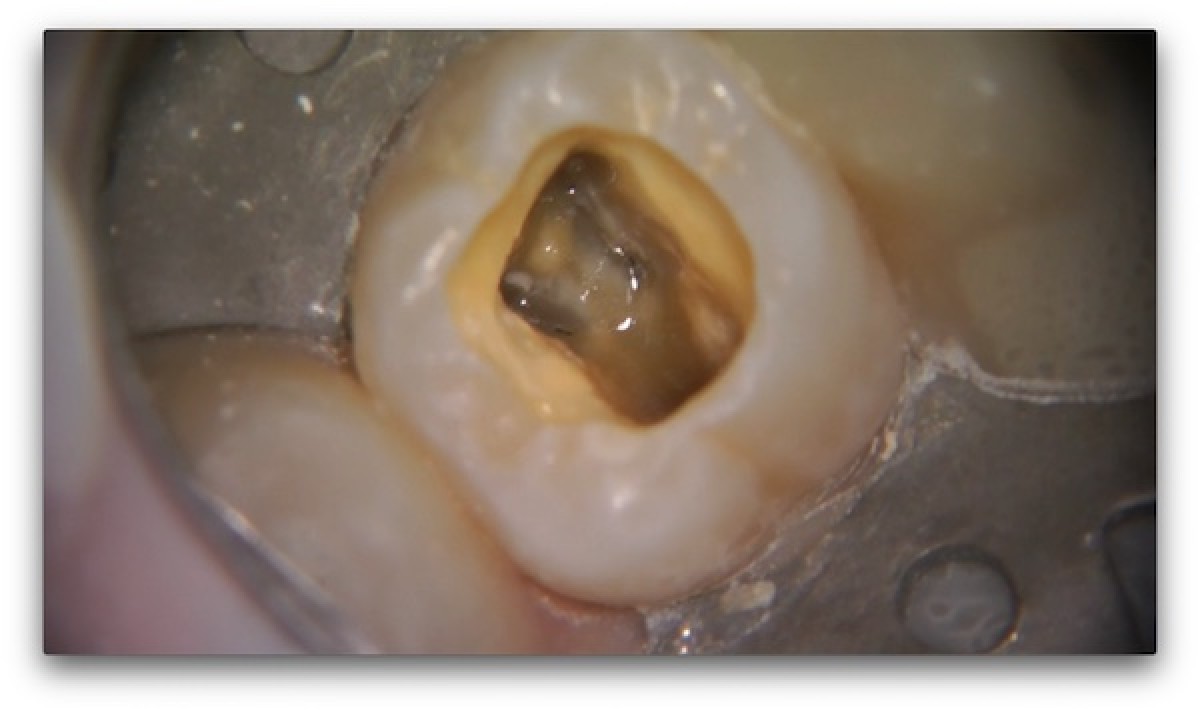

Full rotary endodontic treatment of an necrotic upper first molar YouTube

photo endodontic treatment of dental canals in the lower molar Endo Therapy Molar Ex Rest Endo therapy premolar ex rest: Root canal therapy, also known as endodontic treatment, is a dental procedure that involves removing the infected or inflamed pulp. Endodontic therapy consists of a series of treatments, including removing pulpal tissue, filing and shaping root canals, obturating the root canal. Endodontists and dentists do about 15 million root canals in the united states every.. Endo Therapy Molar Ex Rest.